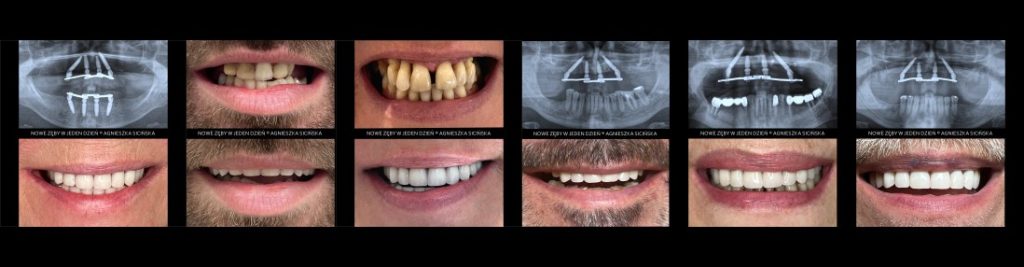

Metamorfozy i doświadczenia pacjentów

Dla wielu osób decyzja o leczeniu staje się łatwiejsza, gdy mogą zobaczyć efekty oraz przeczytać opinie pacjentów, którzy przeszli podobną drogę. Metamorfozy pokazują zmianę estetyczną i funkcjonalną, a opinie pomagają lepiej zrozumieć cały proces leczenia.

Każdy przypadek jest indywidualny i wymaga osobnej kwalifikacji.